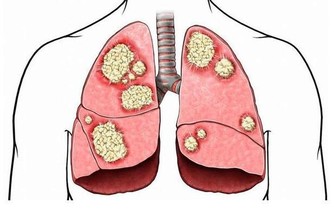

連續三天以上出現凌晨3—5點鐘定時醒來,預示著肺經循行不暢。

建議大家每天敲揉肺經的孔最穴、點揉魚際穴,在痛點處每次操作5—10分鐘。